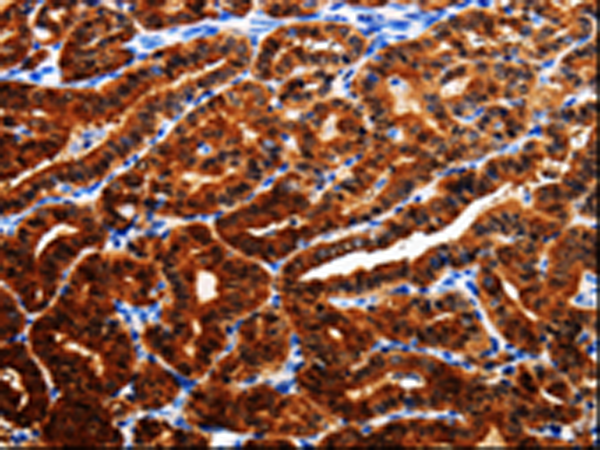

分类: 科研抗体货号: P00094别名: MGC104475应用: IHC反应种属: Human, Mouse